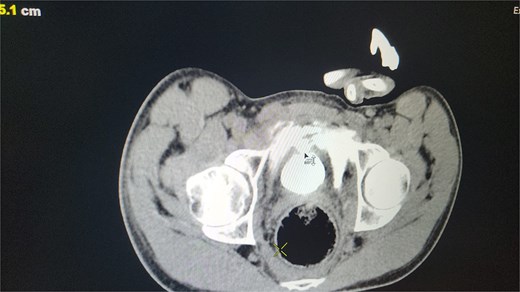

All seven cases of bladder rupture both spontaneous and traumatic were treated surgically via exploratory laparotomy to repair the injury (see Fig. 2). In both types of cases, the ruptured bladder was successfully closed (see Fig. 3). Postoperatively, Redon drain was removed on the second day, and a urinary catheter was maintained for 3 weeks to aid healing.

The image depicts the bladder after surgical repair, showing the successfully sutured rupture site and restored continuity.